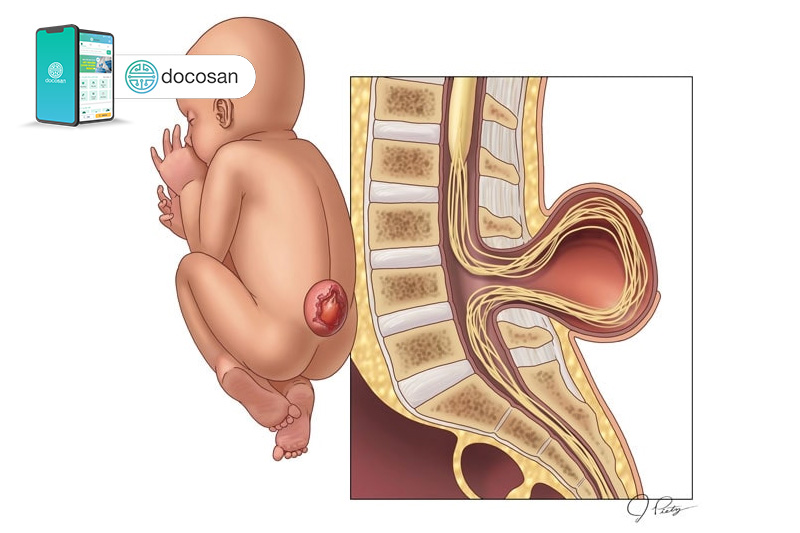

Gai đôi cột sống, hay còn gọi là nứt đốt sống, là một dạng dị tật ống thần kinh. Trong quá trình phát triển của thai nhi, ống thần kinh là cấu trúc sẽ dần phát triển thành não và cột sống của em bé, bắt đầu hình thành vào giai đoạn đầu của thai kỳ và sẽ từ từ đóng lại vào khoảng tuần thứ 4.

Trong bệnh gai đôi cột sống, một phần của ống thần kinh không phát triển và đóng lại đúng cách, dẫn đến các khuyết tật của tuỷ sống và cột sống cho em bé khi chào đời.

Thoát vị tuỷ – màng tuỷ

Thoát vị tủy – màng tủy là thể bệnh nặng nề, nghiêm trọng nhất của bệnh gai đôi cột sống. Ống sống của thai nhi bị hở ở vùng cột sống L5 – S1 và có một túi chất lỏng ở bên ngoài cột sóng.

Thành phần chứa bên trong túi là dịch não tuỷ, màng cứng, màng nhện tuỷ và tuỷ sống và dây thần kinh. Tuỳ theo mức độ thoát vị, thành phần chứa bên trong túi thoát vị và vị trí thoát vị mà người bệnh sẽ có những dấu hiệu khác nhau, ví dụ như: